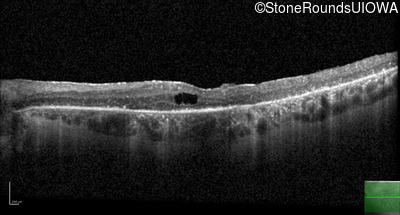

AD Retinitis Pigmentosa (IA1aii)

Age at visit: 60 years

This 60 year old woman first noticed difficulty reading the newspaper about 1 year ago. She also noticed worsening photophobia about that time.

AD Retinitis Pigmentosa PROM1 Arg373Cys CGC>TGC   AD